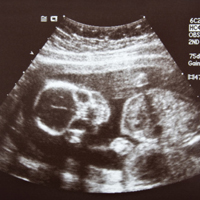

8 неделя беременности фото с узи

8 неделя беременности — заключительная неделя стадии эмбриона. К концу 2 месяца беременности сформированы практически все основные системы и органы малыша, и теперь он будет только развивать их, и расти сам. Мы прощаемся со словом и понятием «эмбрион», потому что теперь он носит гордое название «плод».

Ваша беременность 8 недель. В это время будущий малыш внешне представляет собой маленького человечка-инопланетянина. Личико с огромными глазами без век, выпуклым лбом, большим ртом, приплюснутым носом и выдвинутой вперед нижней челюстью. Хвостик, так смущающий иногда некоторых чрезмерно впечатлительных будущих мам, пропадает, как и жаберные щели. Конечности развиваются быстро, в них уже можно разглядеть не только кисти и стопы, но и сгибы локтей и коленок. Свою окончательную форму принимают желудок и кишечник, головной мозг и сердце. Развивается дыхательный аппарат и центральная нервная система. Человечек выпрямляется, у него появляется шея. Мозг продолжает развиваться (с космической скоростью — за одну минуту производится четверть миллиона нейронов). Сердце эмбриона тоже уже сформировалось.Между ножек появляется бугорок — основа для развития будущих половых органов.

Ваша беременность 8 недель. Все это великолепное создание достигает роста 3–4 см, а вместе с плодными оболочками имеет размеры близкие к размерам куриного яйца и весит уже около 13 грамм. О том какие изменения произойдут с вами и вашим малышом на следующей неделе читайте в статье 9 неделя беременности